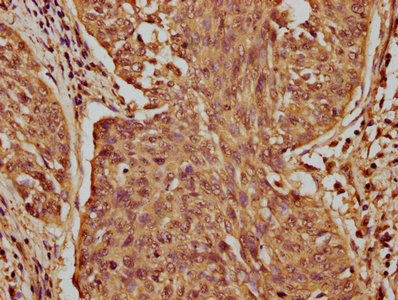

IHC image of CSB-PA773036LA01HU diluted at 1:100 and staining in paraffin-embedded human cervical cancer performed on a Leica BondTM system. After dewaxing and hydration, antigen retrieval was mediated by high pressure in a citrate buffer (pH 6.0). Section was blocked with 10% normal goat serum 30min at RT. Then primary antibody (1% BSA) was incubated at 4°C overnight. The primary is detected by a biotinylated secondary antibody and visualized using an HRP conjugated SP system.